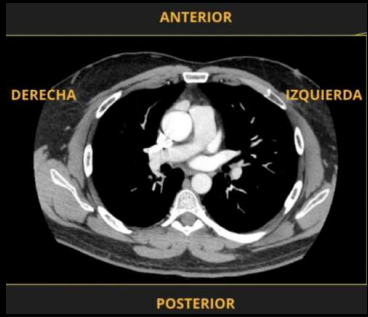

<p>Por el corte ___ pordemos identificar a la TC.</p>

Por el corte ___ pordemos identificar a la TC.

AXIAL

<p>Estudio y nomenclatura</p>

Estudio y nomenclatura

TC, Hiperdensos.